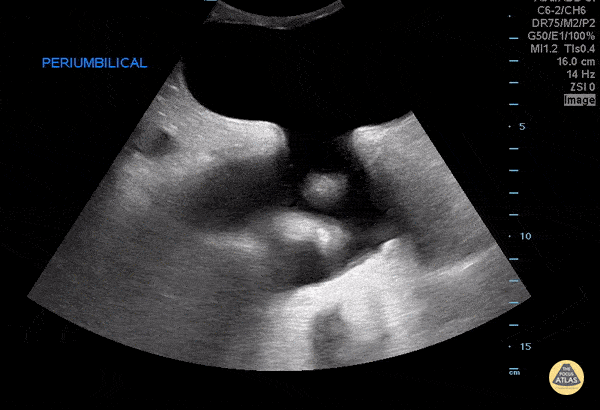

Bowel-GI - Fluid Filled Periumbilical Hernia

27 year old male with a history of cirrhosis presenting with increased swelling of the periumbilical area. A bedside ultrasound was performed demonstrating a fluid filled hernia sac from the patient’s known ascites. Mario Corro, MD, PGY-3 & Josh Greenstein, MD Staten Island University Hospital